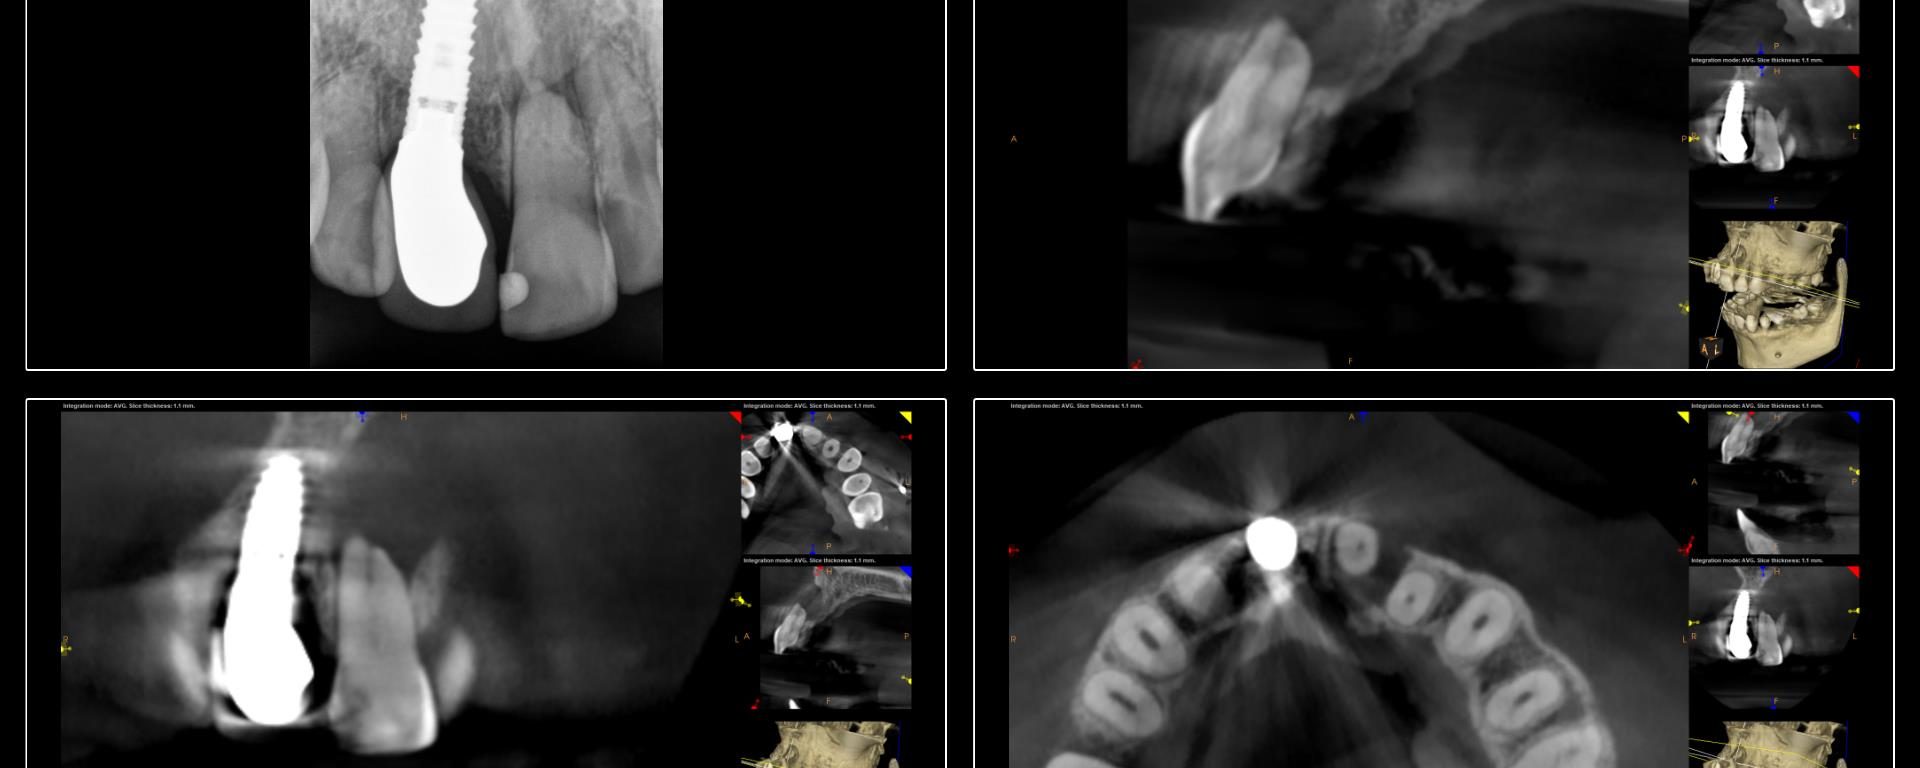

Dynamically Guided Endodontic Access

July 31, 2018 13 comments

Dynamic navigation has been in dentistry for many years. It remains in its infancy in endodontics but is proving to be very helpful for the access of calcified teeth. This is a case from yesterday in which dynamic navigation was used to allow for a conservative access while locating the calcified canal. -Charles